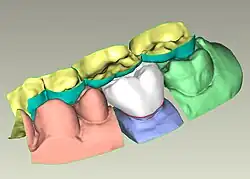

La conception assistée par ordinateur trouve une application en odontologie. La CAO fait suite à l'étape d'acquisition numérique, réalisée grâce à un dispositif de numérisation associé à des programmes de traitement des données. Plusieurs solutions de numérisation existent, comme une caméra intra-orale (empreinte numérique des arcades dentaires du patient) ou un scanner de modèle en plâtre.

L'étape de CAO se compose de programmes informatiques qui permettent la conception de la restauration prothétique virtuelle (couronne, bridge, onlay, prothèse amovible) sur le modèle virtuel correspondant aux arcades du patients. La conception est réalisée via l'utilisation de dents et de restaurations types provenant d'une base de données. La restauration est adaptée au modèle via des modules d’aide à la conception permettant la création des contacts avec les dents adjacentes et antagonistes (simulation de l’occlusion), la définition de l'espacement entre la restauration et le modèle, le tracé de la zone d'arrêt de la prothèse (limite cervicale) etc[5].